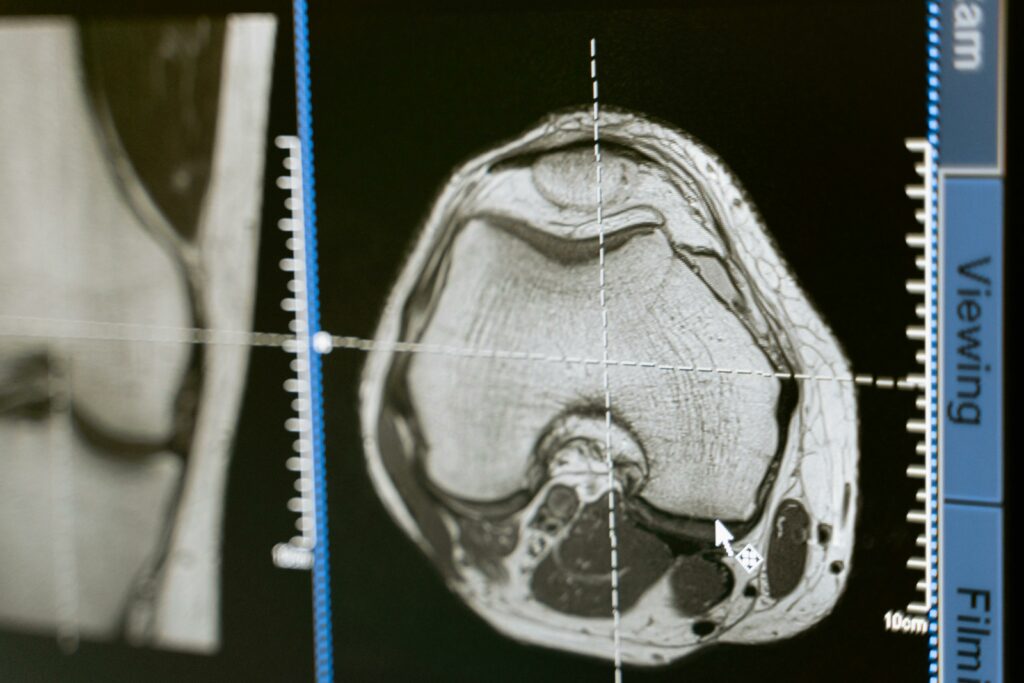

L’imagerie par résonance magnétique utilise un champ magnétique puissant et des ondes radio pour produire des images très détaillées des tissus. Elle offre une excellente caractérisation anatomique et tissulaire, avec des séquences adaptées (T1, T2, diffusion, etc.) permettant d’explorer inflammation, œdème, hémorragie, lésions ligamentaires, atteintes neurologiques, ou encore certaines pathologies tumorales.

Ses points forts : une précision élevée, une exploration multiplanaire, et une très bonne analyse des parties molles profondes (cerveau, moelle, pelvis, articulations complexes). Elle est également non irradiante. Elle permet aussi d’analyser certaines atteintes inflammatoires ou traumatiques avec une excellente sensibilité.

Sur le plan de la précision anatomique, l’IRM est souvent supérieure pour les structures profondes et complexes (rachis, cerveau, certaines articulations) et pour l’analyse fine de tissus où l’échographie est limitée par la profondeur, l’os ou l’air. L’échographie, elle, excelle dans l’analyse des structures superficielles, des organes abdominaux accessibles, et dans l’évaluation en temps réel : elle permet une corrélation immédiate avec la douleur, la palpation, et une analyse dynamique. La qualité des images et leur interprétation conditionnent le diagnostic. Comparer les images au cours du temps peut aussi contribuer au suivi.

En revanche, l’échographie ne peut pas se substituer à l’IRM pour l’étude du système nerveux central, de la moelle, de certaines pathologies profondes du bassin, ou pour des cartographies lésionnelles complexes (ex. certaines lésions méniscales/ligamentaires selon le contexte, pathologies médullaires, bilan tumoral nécessitant une caractérisation avancée). Dans ces situations, l’IRM est souvent l’examen de référence.